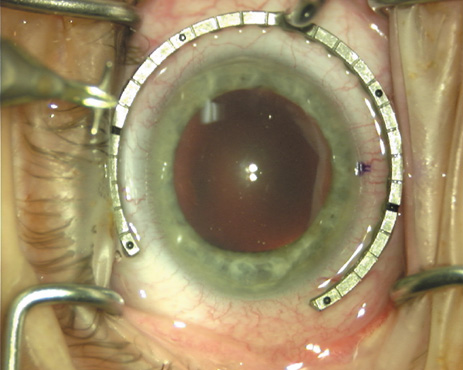

Case 1 is a 68-year-old male who presented for right cataract surgery. His refraction was −1.00 +2.25 × 80 and was recorded as reliable, consistent with his modest cataract density. Keratometry readings were 44.75 × 75 and 43.00 × 165. Corneal topography confirmed slightly more than 2.00 D of regular and slightly oblique cylinder. Consulting the nomogram, a plan was devised for a pair of LRIs to be centered over the 75-degree axis, with each incision delineating 45 degrees of arc. A single plane phaco incision was used and maintained at a size of less than 3.2 mm (Figs. 811).

Fig. 10. The single footplate diamond blade is inserted perpendicular to the corneal surface and at the peripheral most extent of clear corneal tissue. In this case, the nomogram calls for arcuate incisions of 45 degrees. Therefore, the incision is begun approximately 22.5 degrees to one side of the broad hash mark. (Reprinted from Hardten DR, Lindstrom RL, Davis EA. Phakic Intraocular Lenses: Principles and Practice. Thorofare, NJ: SLACK Incorporated, 2004, with permission.)